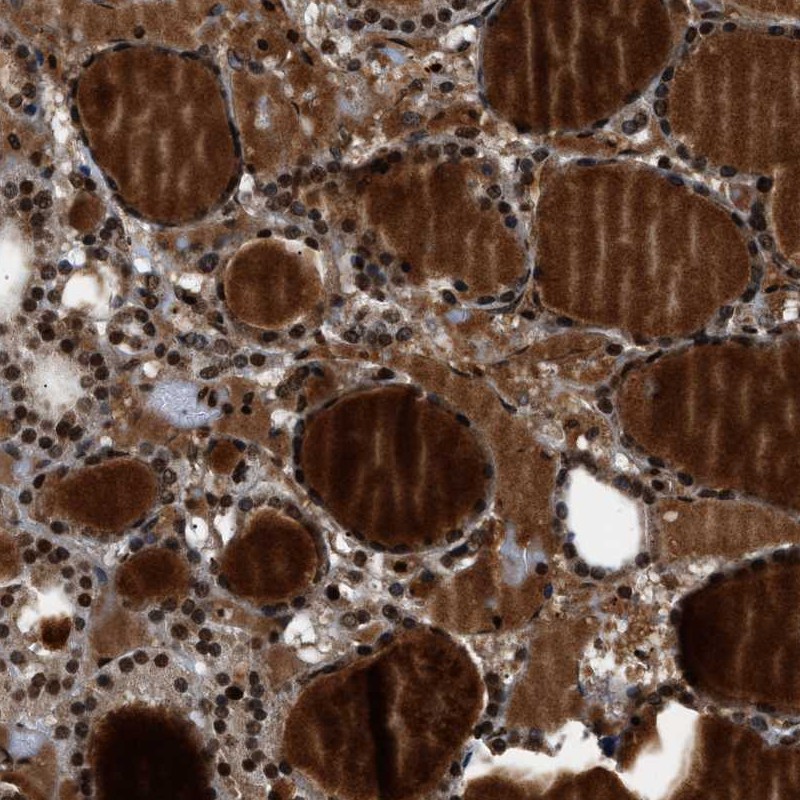

- Experimental details

- Immunohistochemical staining of human thyroid gland shows nuclear positivity in glandular cells and distinct positivity of colloids.

- Validation comment

- Staining pattern partly consistent with experimental and/or bioinformatic data.